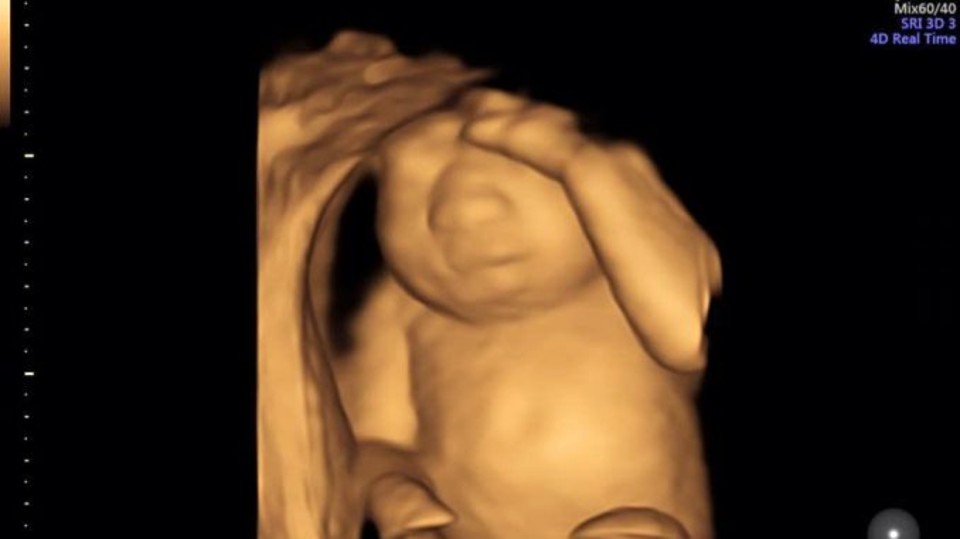

At the 19-week ultrasound, the doctors discovered that Eva had a rare disease, but they chose not to terminate the pregnancy, but to continue it. Eva was born in May 2016 and until then her mother continued to give news about the pregnancy on Facebook. She wrote the following in such a post:

“This is our daughter’s, perfect heart. She has perfect feet and perfect hands. She has perfect kidneys, perfect lungs, and a perfect liver. Sadly, she doesn’t have a perfect brain. We found out recently she has anencephaly and is terminal.